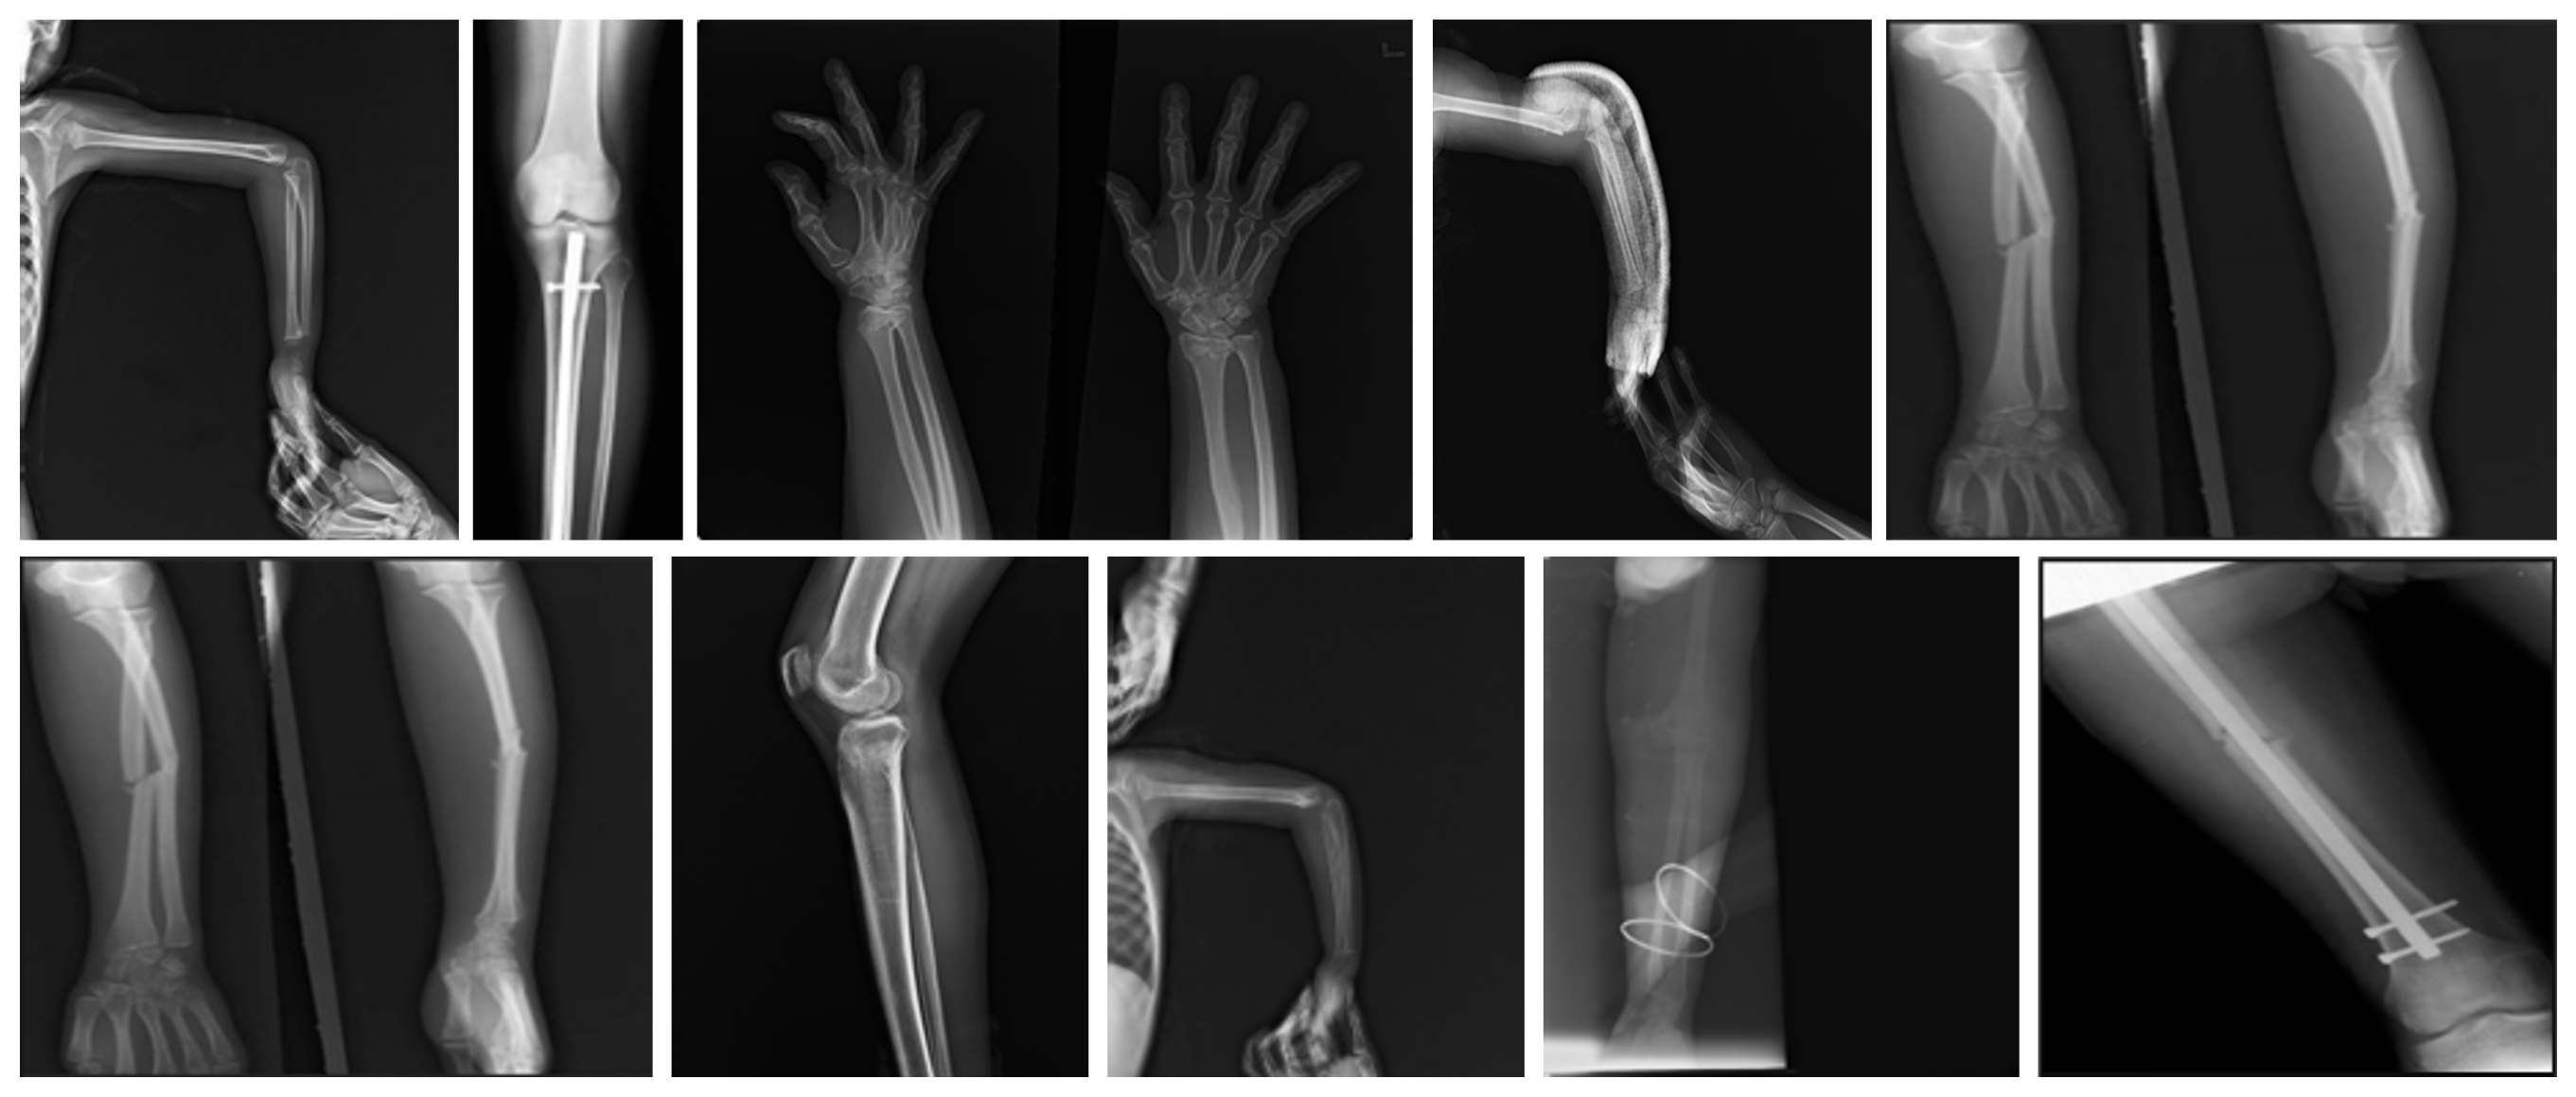

Refer to caption

Figure 1: Example X-ray images from the FracAtlas dataset showing fractured and non-fractured bones.